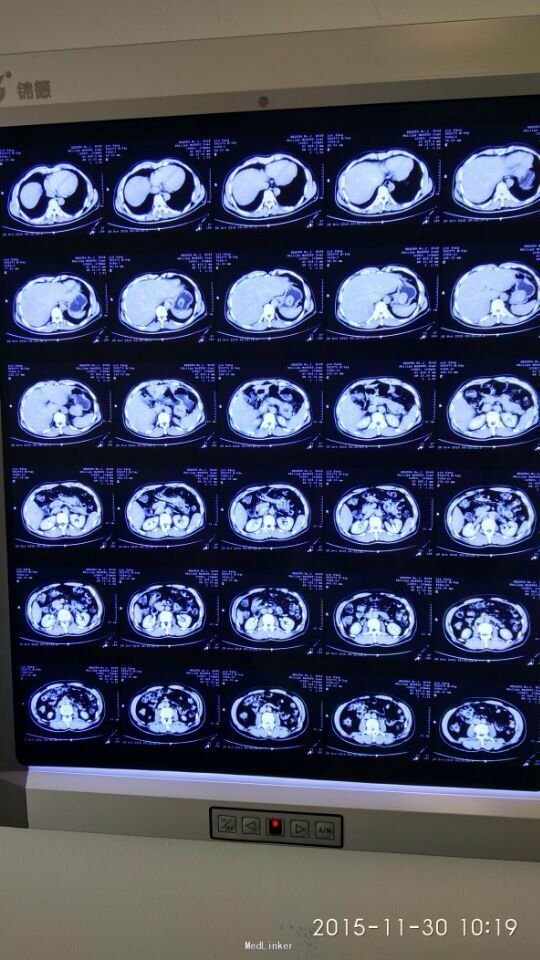

间断性上腹部隐痛,加重两月余。 于15年前左上腹间断隐痛,可忍,伴肩背部放射,活动后缓解,无恶心呕吐,大小便正常,未行特殊处理。2月前,上述症状出现并加重,伴腹泻,伴肩背部放射,无皮肤粘膜黄染。

胃间质瘤 拟行胃间质瘤切除术

瘤体较大,超过5cm,术中注意与胰腺关系,如果压迫胰腺或压迫脾脏血管,是否考虑部分胰腺切除及脾切除,是否考虑胃空肠吻合。